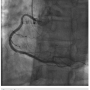

There was transient loss of flow in the posterior left ventricular branch (PLV), which was wired with a Fielder XT wire, and then changed out for a Pilot wire through an over-the-wire balloon (Figure 7). We exchanged for a Runthrough wire into the distal posterior descending coronary artery (PDA). The Corsair was removed from the collateral, and we took the guide and wire from the left system. Two additional 3.0 x 28 mm Promus drug-eluting stents were placed distally prior to the bifurcation. After stent placement, there was good flow in the distal vessel. A gap in between the stents was covered with a 3.0 x 8 mm Promus drug-eluting stent. We then

post dilated with a 3.25 x 15 mm Quantum balloon (Boston Scientific) at high pressure (Figures 8-9). Because of a pseudo lesion in the proximal vessel, we exchanged out for a Judkins right (JR) 4 guide and gave 200 mcg intracoronary (IC) nitroglycerin. Angiography revealed TIMI-3 flow in the vessel without any perforation or embolization (Figure 10). The patient tolerated the procedure well. The guide was removed and a TR Band (Terumo) was placed over bilateral radials. The patient has done well clinically, and is approximately 6 months post PCI with excellent functional capacity and no ischemic symptoms.